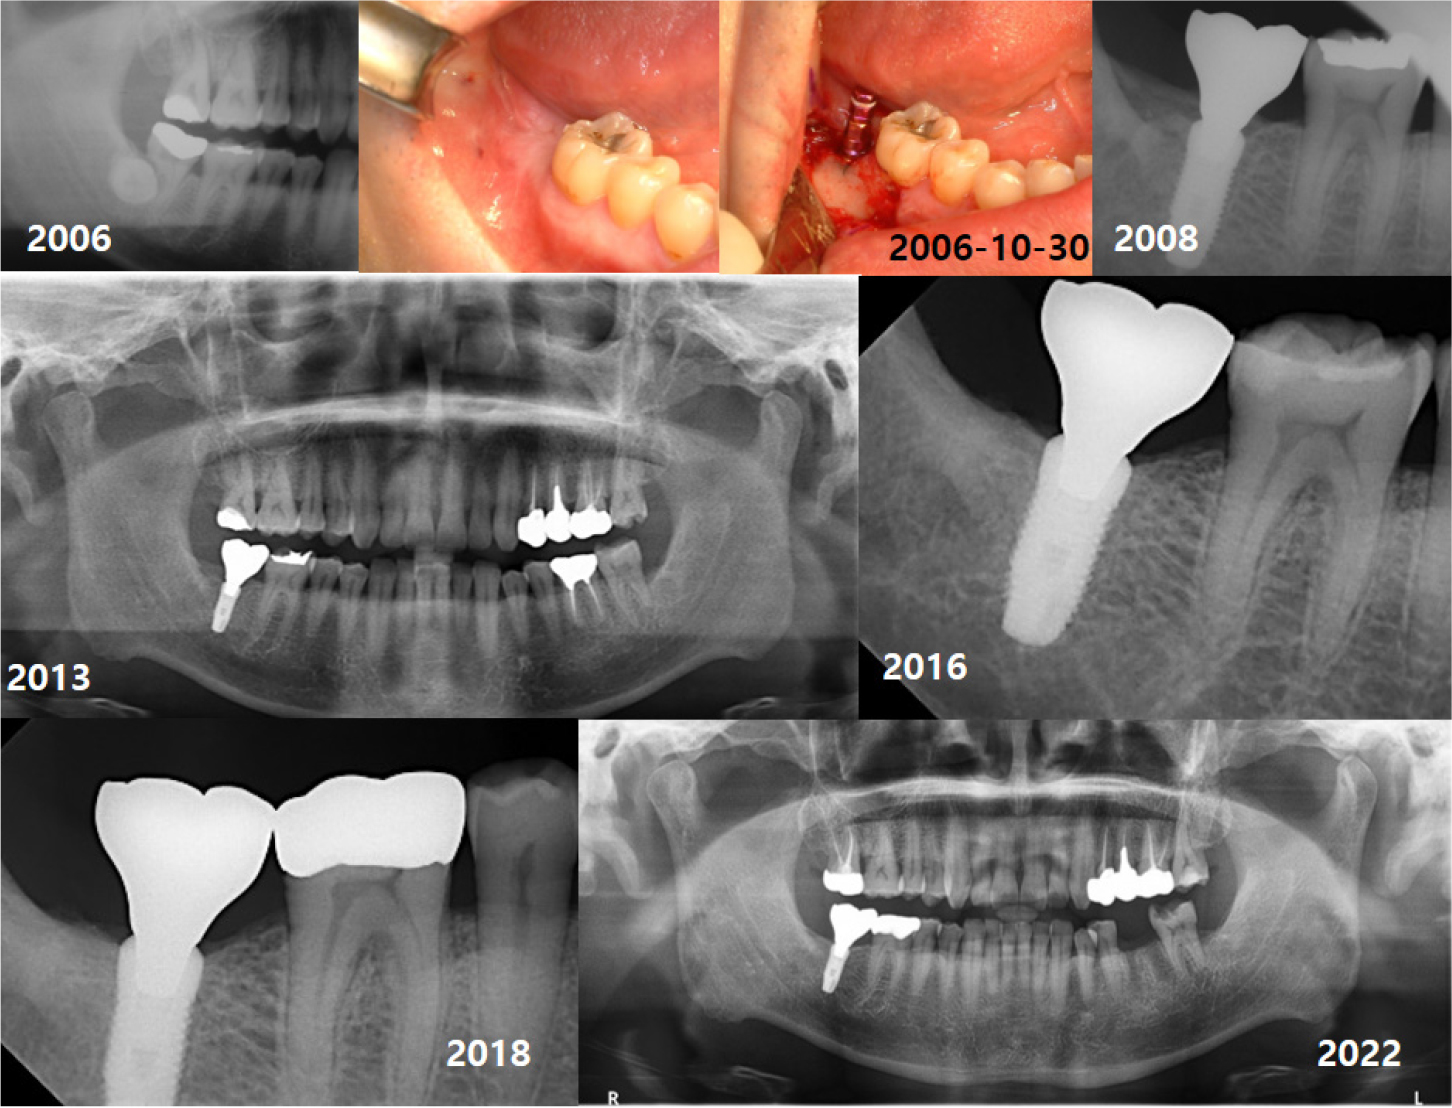

A total of 147 implants were placed in eight types (internal type: Implantium, Astra, Superline, TS III CA, Straumann, Luna, external type: Brånemark, US II), and all the implants were bone-level type. A second surgery was performed three months after first surgery in case of two-stage implants. Impression was taken two weeks after second surgery, and conventional prosthetic treatment was performed. Follow-ups were performed at three-month interval for the first year, then at six-month intervals for the next year, and then one-year intervals with panorama or periapical radiography (Fig.1). The criteria for implant survival was evaluated on the basis of four factors: absence of persistent pain, absence of mobility of implant, absence of continuous radiographic bone loss, and absence of uncontrolled exudate.8 The CSR was calculated using life-table analysis. Also, comparisons in CSRs between implant diameter and length, and GBR were performed using Log Rank test. p < .05 was considered significant.

In the first case of failure, the patient had no specific medical history. The implant was removed at 6 years and 11 months (Fig. 3). In the second case, the patient had diabetes mellitus, and a smoking history. Also, GBR was performed with Xenograft and Bio-Oss. The implant was removed at 8 years and 3 months (Fig. 4). In the third case, the patient had radiotherapy history for tonsil cancer. The implant was removed at 4 years and 10 months (Fig. 5). In the fourth case, the patient had diabetes mellitus. The implant was removed, and another implant was immediately placed at four months (Fig. 6).